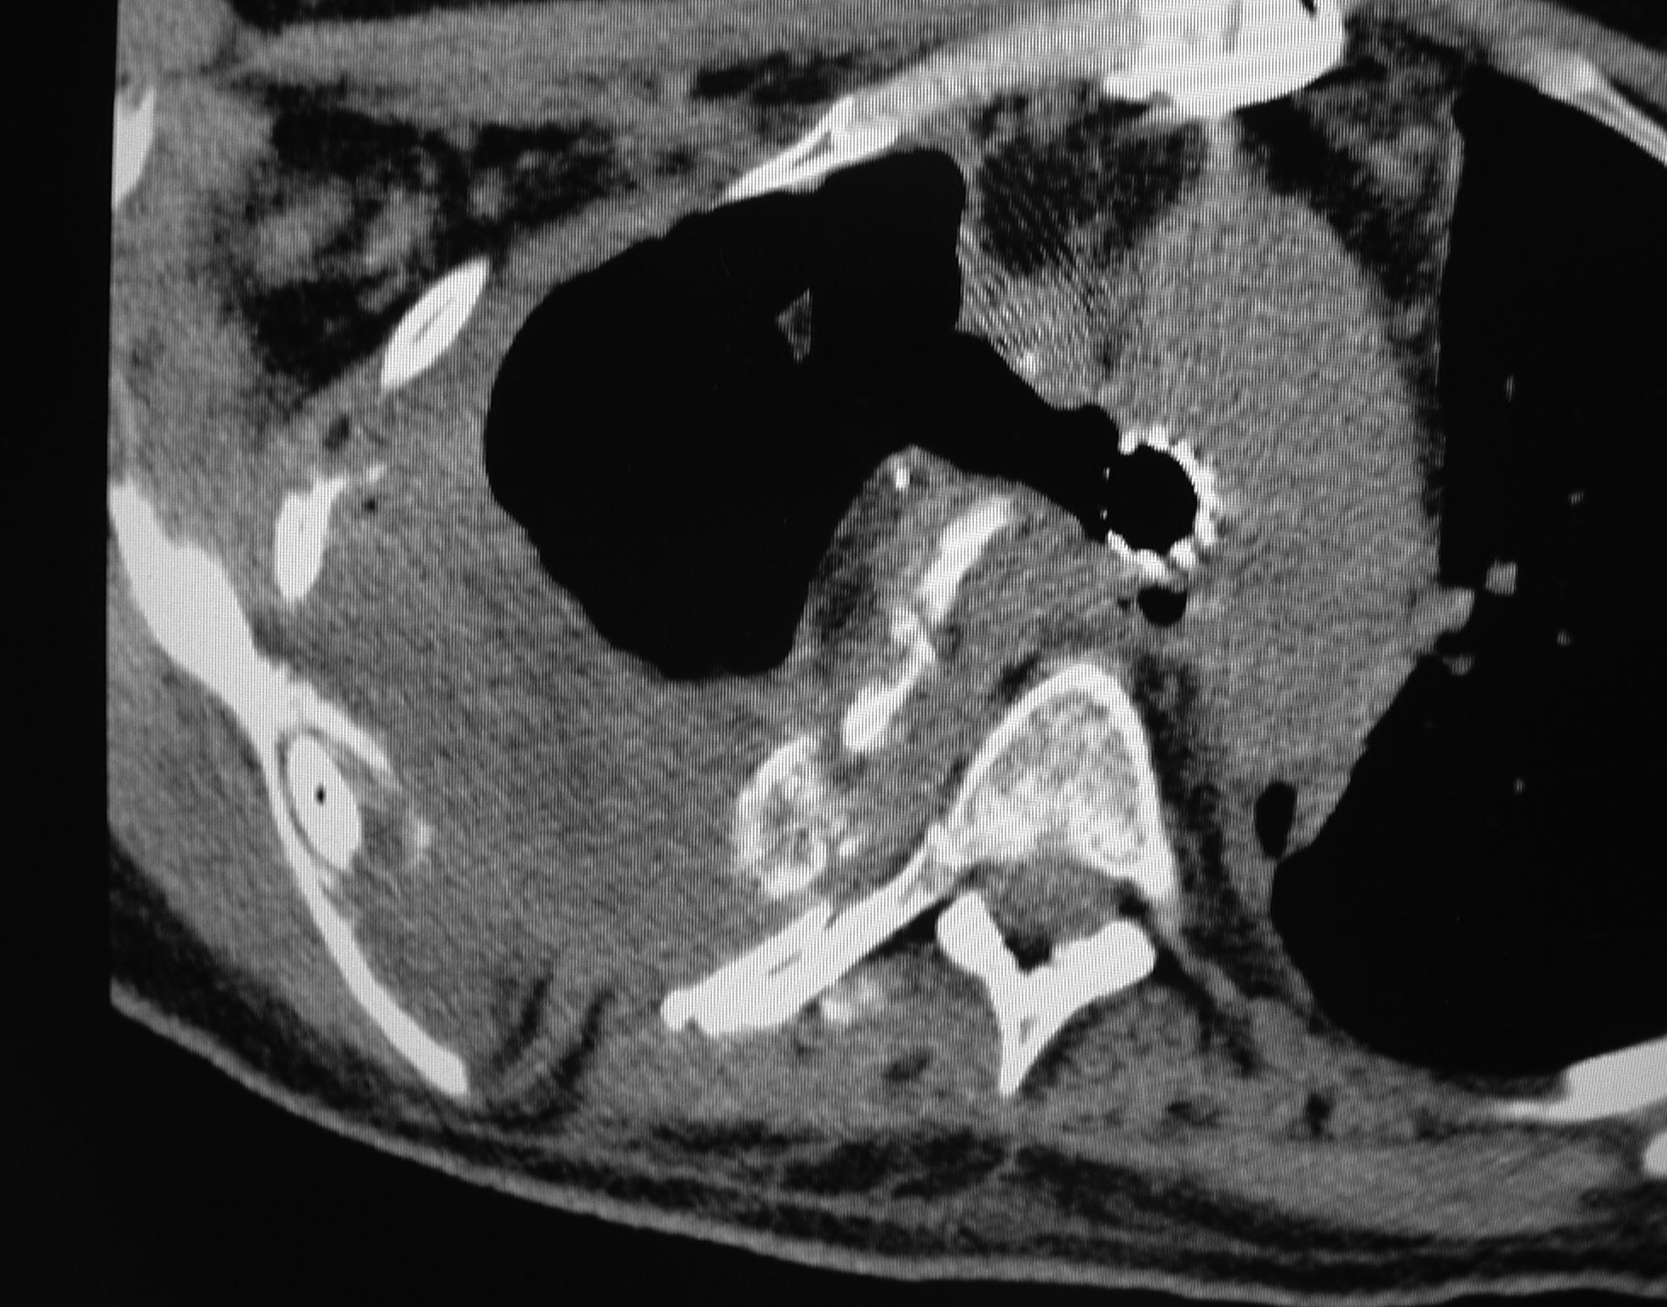

She unfortunately developed recurrent bronchopleural fistula about 4 months after the first flap surgery, with a small open wound on her right chest and a persistent air leak. She was otherwise doing well with no evidence of infection ( Fig. 24.7 ). Repeated chest CT scans showed a less optimal filling of the pleural cavity ( Fig. 24.8 ). At this point, it became clear that additional well-vascularized tissue would be required not only to seal the recurrent bronchopleural fistula but also to obliterate the remaining dead space within the thoracic cavity. She was brought to the operating room for the second intrathoracic flap transfer. During exploration, the recurrent bronchopleural fistula was identified ( Figs. 24.9 and 24.10 ) and repaired again by the thoracic surgery service with additional suture and fascial patch graft ( Fig. 24.11 ). Because of the previous right thoracotomy, the left latissimus dorsi myocutaneous flap was selected and elevated as a free flap ( Fig. 24.12 ). The right thoracodorsal vessels were explored for the recipient vessels. After successful end-to-end microvascular anastomoses for both artery and vein, the entire flap appeared to be well perfused ( Fig. 24.13 ). The de-epithelialized flap could be placed freely anywhere inside the pleural cavity. The repair site of the recurrent fistula was covered with the muscular portion of the flap and the remaining dead space was completely obliterated by the flap with the de-epithelized portion facing out ( Fig. 24.14 ). With concerns of the flap being buried inside the chest, it was observed for an hour in the operating room after both microvascular anastomoses before the chest wound was closed. It reassured the surgeon that both microvascular anastomoses were patent and there were no technical errors in the free tissue transfer. The chest wound was closed again in two layers after local tissue rearrangement ( Fig. 24.15 ). The patient tolerated the entire procedure well and was extubated the next day. She was found to have no further air leak after the second flap surgery and was discharged from the hospital 2 weeks postoperatively